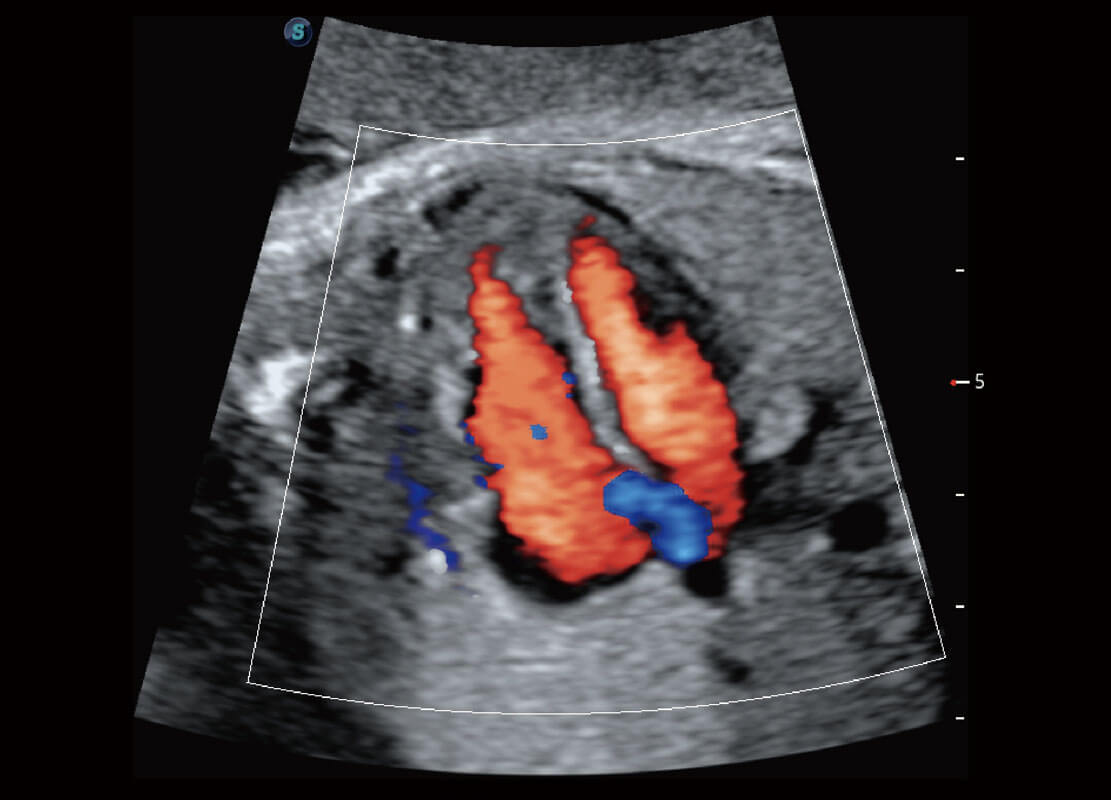

P60为盆底超声检查提供应用方案,多种腔内及腹部容积探头提供从二维、三维到四维的优异图像品质,实时快速三维容积数据获取,专业的测量工具包等人性化设计,为超声医生诊断提供有力保障。

Lev.Hiat A-r: 16.33 cm2

Lev.Hiat H-r: 53.70 mm

Lev.Hiat W-r: 43.96 mm

Lt-LUG-r: 24.16 mm

Rt-LUG-r: 19.94 mm

能够简化盆底检查的操作流程,可在二维模式及三维成像模式下实现一键自动提取出标准切面、自动识别当前切面、自动测量,提升盆底检查的高效性,同时也能让青年医生快捷的获得准确的检查结果。